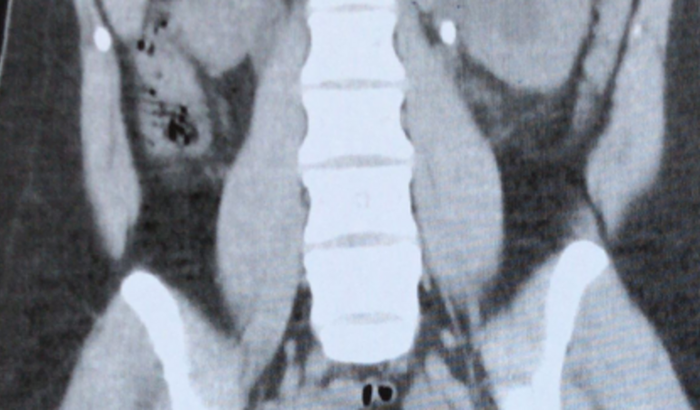

Oii pessoal, Sou Amanda moro em Itaú de Minas, preciso fazer uma cirurgia ureterorrenolitotripsia flexível unilateral. Venho passando muito mal por esses dias, infelizmente não tenho condições financeiras para pagar a cirurgia. Preciso de 12.624,80 para arcar com as despesas hospitalares.Desde já agradeço a todos que puderem me ajudar com qualquer quantia!!